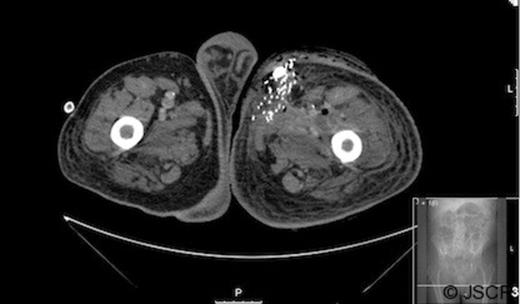

Radiographs confirmed subcutaneous gas associated with the swelling (figure 1). The patient was consented for incision and drainage of the collection, where it was noted that gas bubbles were released on initial stab incision. Copious grey watery fluid was drained from the cavity which appeared to track under the inguinal ligament. Cavity fluid and biopsy specimens were sent for microscopy, culture and sensitivity. The cavity was packed and broad spectrum antibiotics were started following consultation with a microbiologist. A pelvic CT scan with contrast was arranged (figure 2–4), which confirmed a vesicocutaneous fistula.

Figures 2, 3, and 4 are axial, sagittal, and coronal views, respectively, of computed tomography with contrast introduced by urinary catheter. This CT cystogram shows a leak/fistula at the low anterior bladder wall. The fistula has a communication with the pubic symphysis and a collection lies anterior to this. The tract extends distally, communicating with the cavity in the left anteromedial aspect of the thigh.